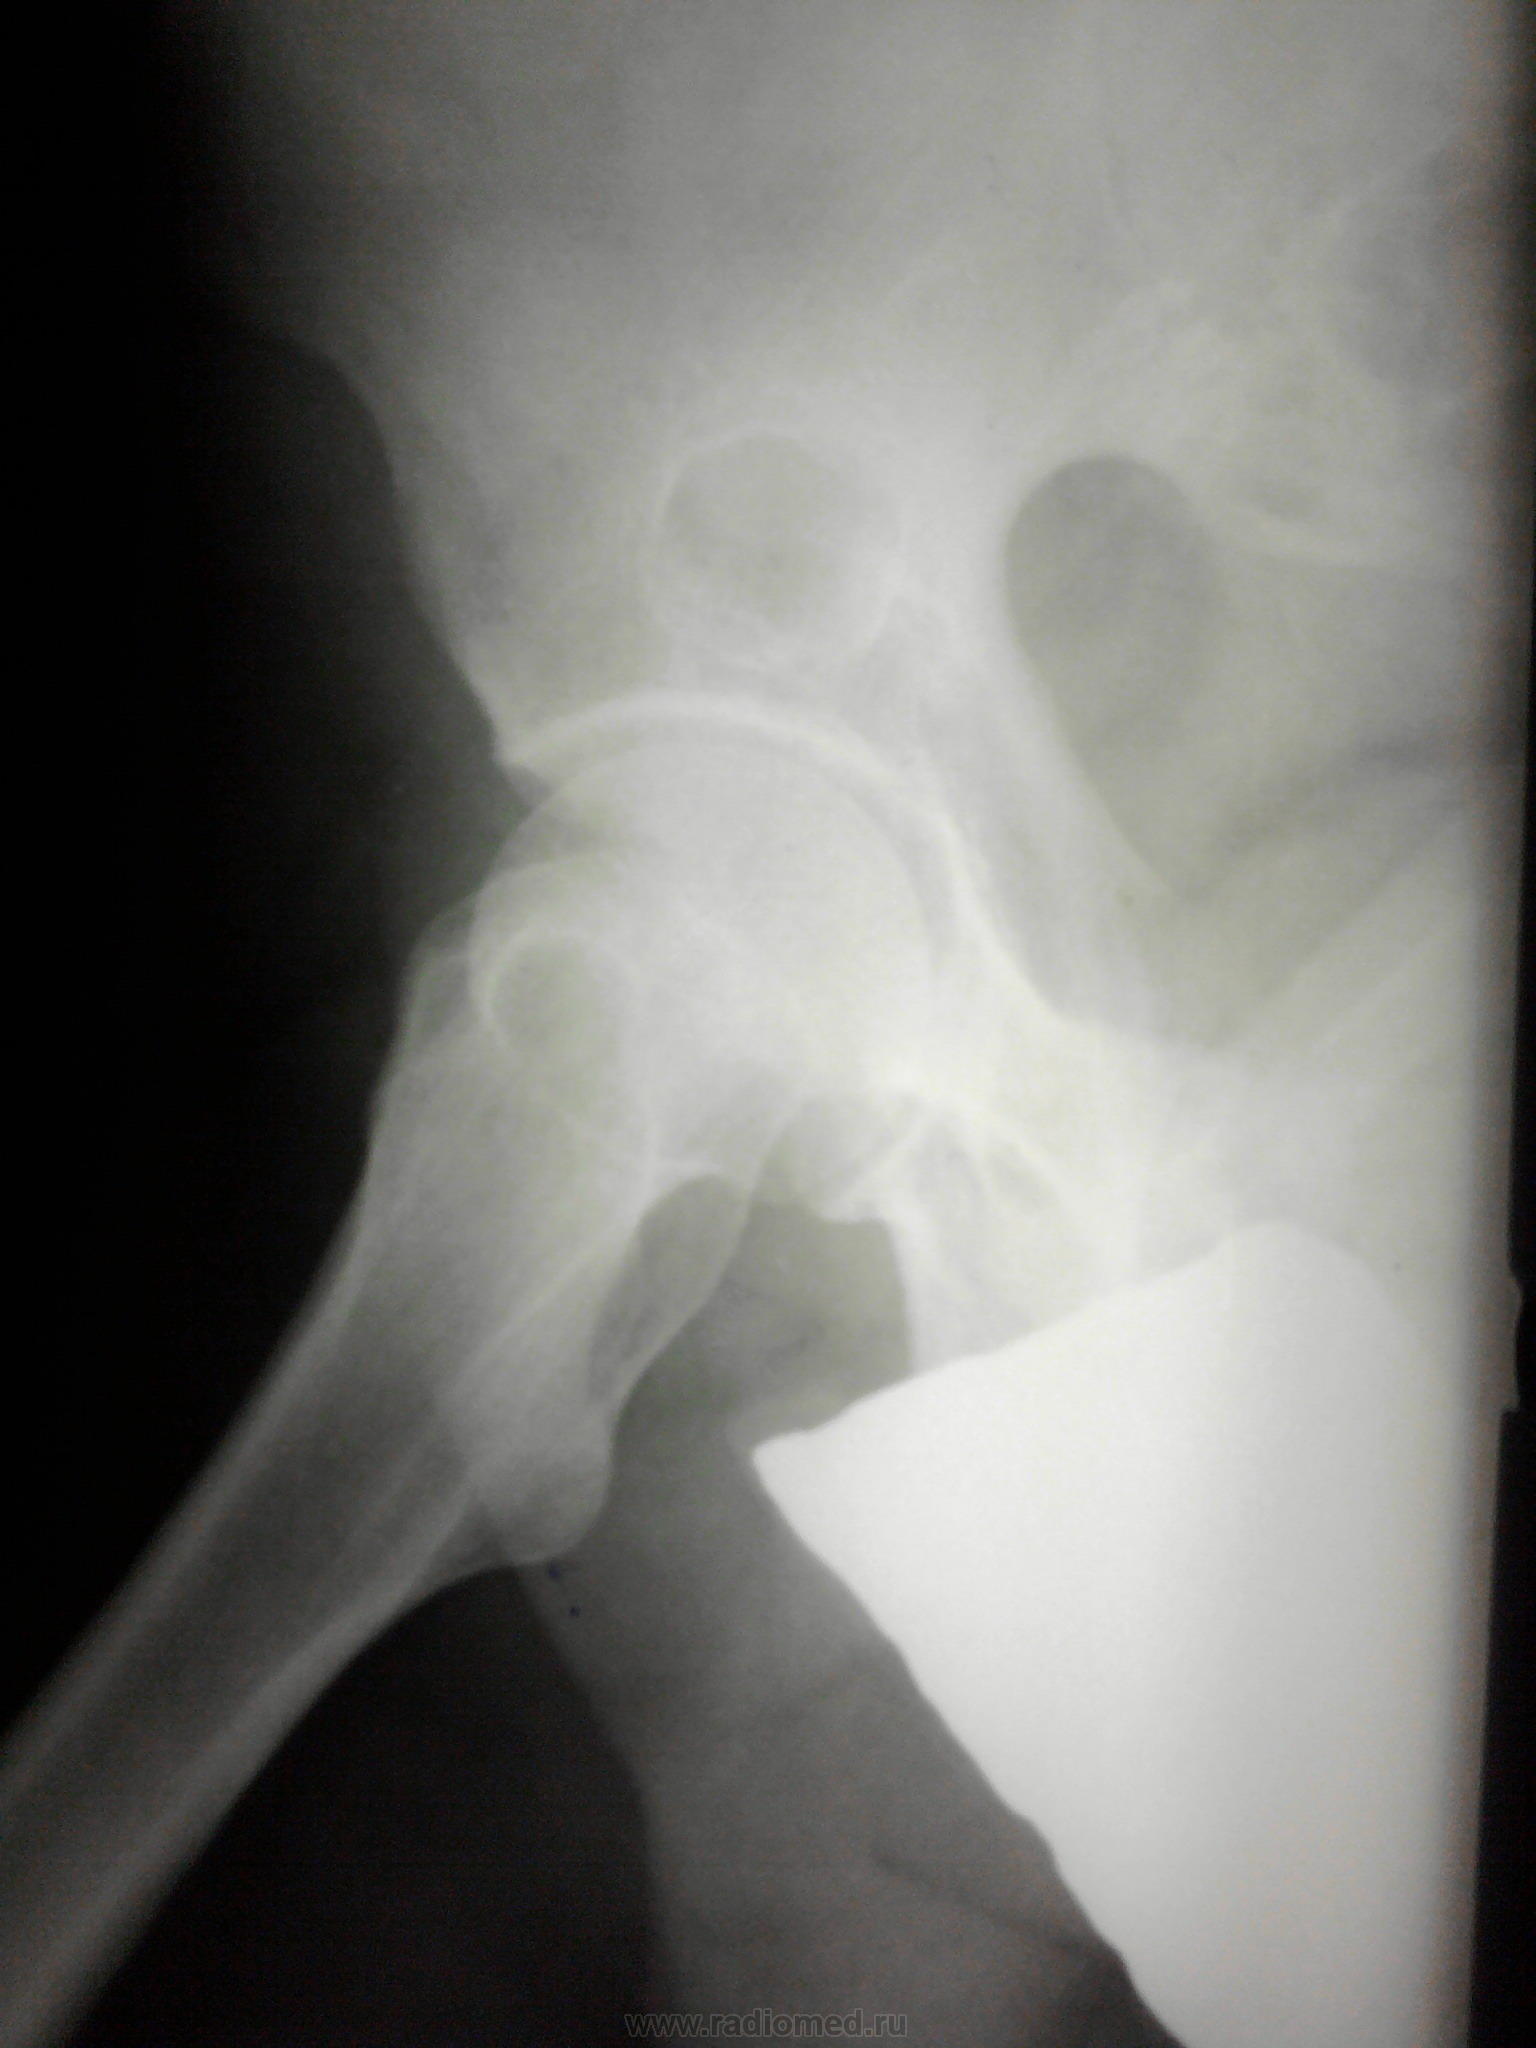

Двухсторонние литические очаги, с четкими, местами склерозироваными контурами. Старый консолидированый перелом левой бедренной кости, после металлоостеосинтеза металлической пластиной. Миеломная или мтс проявили бы себя более агрессивной деструкцией.

tatyana, Вам "зачет"! Здесь действительнро болезнь Реклингхаузена. Наблюдаю данного пациента лет 7. За это время его патологический перелом левой бедренной кости так и не срастается, приобретая все более атрофичный вид в виде перетяжки на уровне излома, потому и держат с металлом до сих пор. Классическая "пастушья палка". Справа в теле подвздошной кости и (менее выраженно) ближе к задней нижней ости, а также в большом вертеле также имеются литические очаги, относительно стабильные за время наблюдения.

"самоуверенность дилетантов - предмет зависти профессионалов"